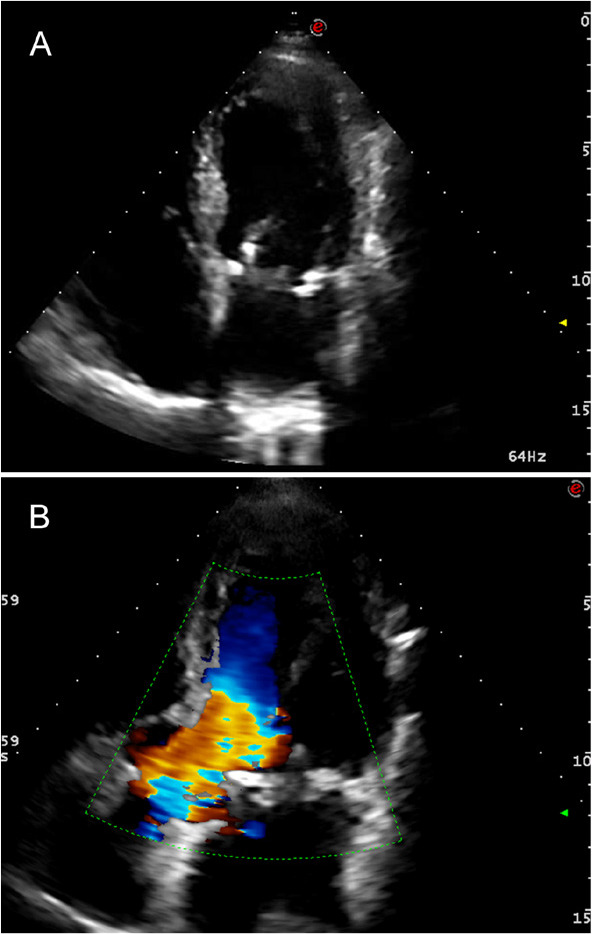

心肌血运重建术患者应治疗严重的功能性二尖瓣返流。当置换被认为是最好的治疗选择时,保存二尖瓣下装置是至关重要的,特别是在急诊情况下,因为它在保存左右心室的几何形状和功能方面起着主要作用。在这里,我们提出了一种简单而快速的技术,在接受生物假体二尖瓣置换术的患者中,瓣下器官被完整地保存。

Severe functional mitral valve regurgitation should be treated in patients undergoing myocardial revascularization. When replacement is considered the best therapeutic option, preservation of the mitral subvalvular apparatus is crucial, especially in the emergency setting, because of its primary role in preserving geometry and function of left and right ventricles. Here we present a simple and quick technique, where subvalvular apparatus is preserved in toto in patients undergoing mitral valve replacement with a bioprosthesis.